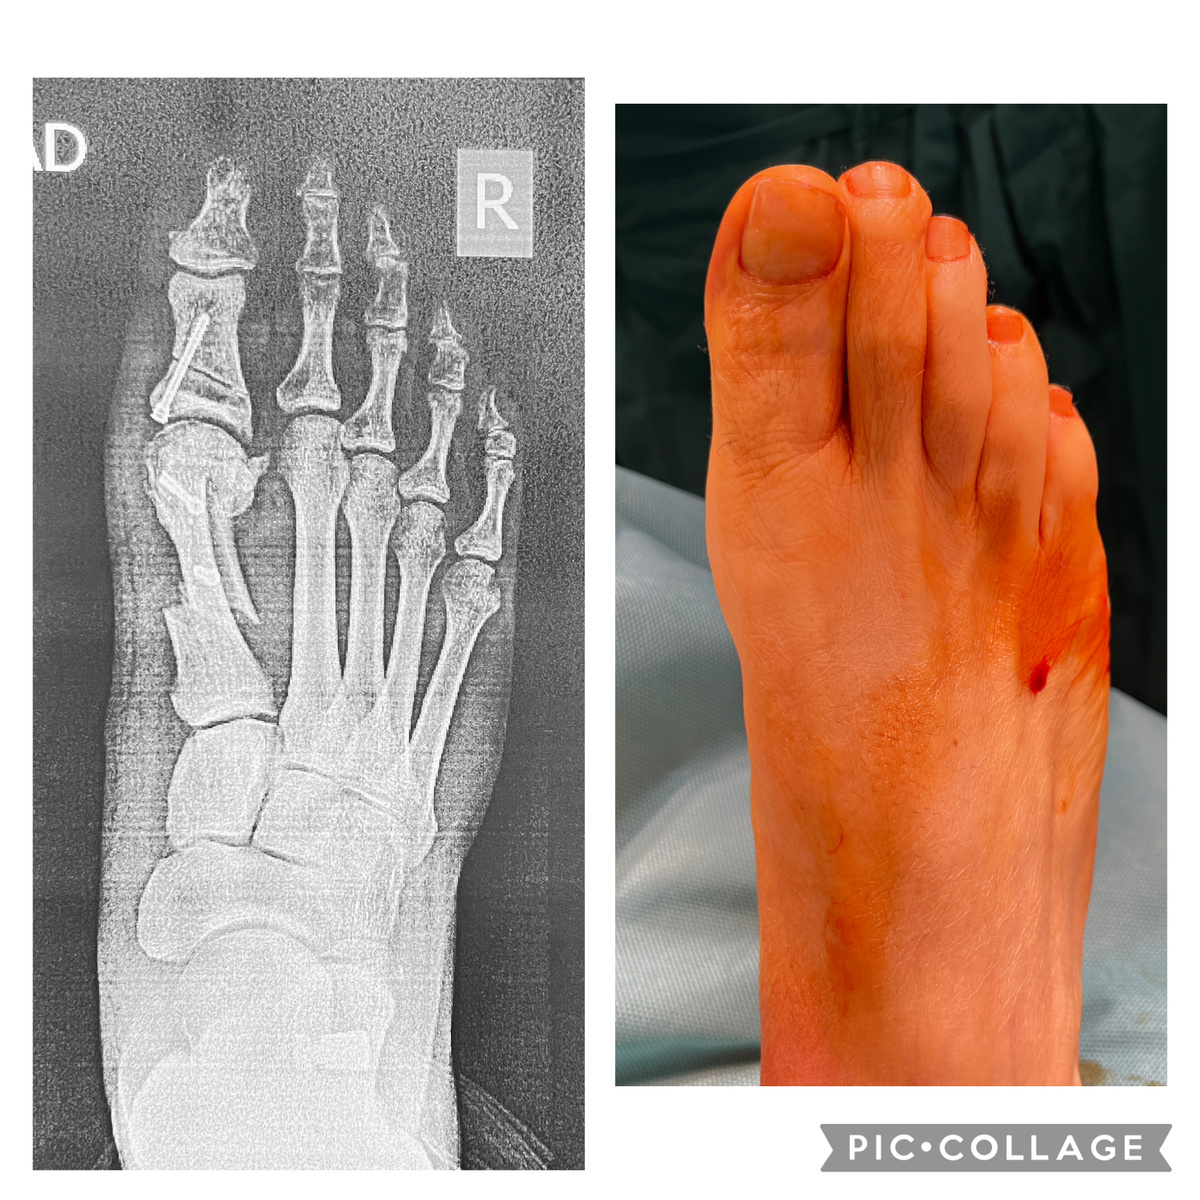

Немного (или много) сумбурный пост про стопы и вальгус стоп. Первой картинкой поставил скрин со своего поста с клиническим случаем в ВК. Если присмотреться - видно, там речь идет о небольшой хирургии - внедрении импланта между таранной и пяточной костями, что сразу же формирует нормальный продольный свод и заставляет стопы и стоять вертикально (в заднем отделе), и нагружаться правильно. Сумбур сейчас будет оттого, что на днях купили дочке две пары кроссовок, а сегодня удалил имплант пациенту, которого оперировал в 2016 году. Казалось бы, какая связь? Читаем, начну с конца. 2016 Пациент за 50, пришёл за коррекцией переднего отдела стоп - шишка, наружное отклонение больших пальцев. Это всегда видимая часть айсберга, не специалист невооруженным глазом видит. Менее видимая (для не специалиста) часть - это коллапс продольного свода и вальгусная установка стоп. Соответственно, исправить отклонение первых пальцев и «убрать шишки» - не проблема. Проблема - проигнорировать всё остальное, ибо з

К сожалению, не нашел исходных данных, только рентген сразу после операции. Справа - вид стопы сейчас

Стрелкой показан имплант

Вот такой шикарный свод. И следов шва, кстати, не видно